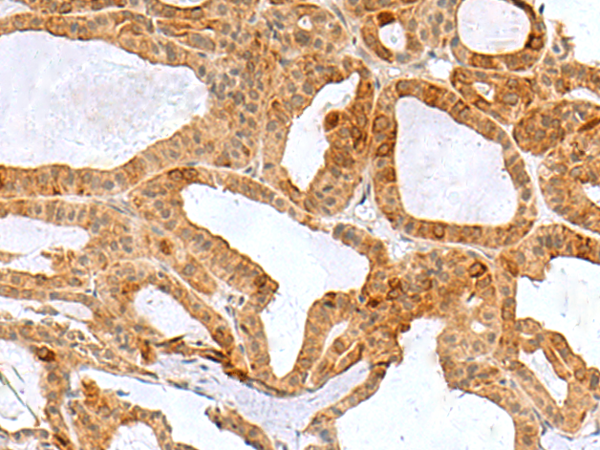

分类: 科研抗体货号: P10219别名: L3MBT; H-l(3)mbt-l应用: WB,IHC反应种属: Human, Mouse, Rat